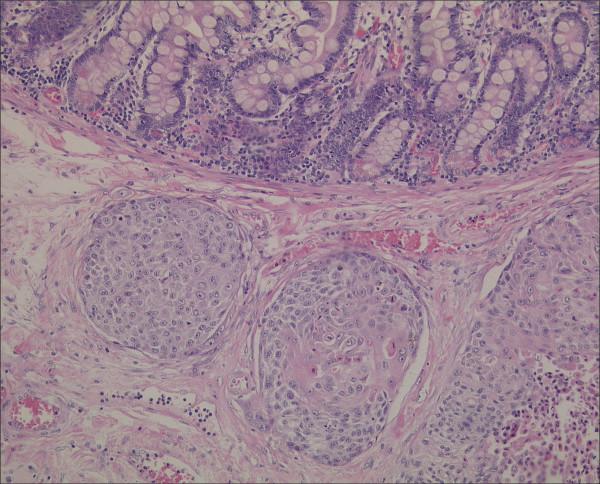

The case involved a 56-year-old man with a squamous cell carcinoma of the lung (stage IV) that had been treated with chemotherapy. He presented fourteen months after diagnosis with an acute abdominal pain. Abdominal CT-scan demonstrated a perforated jejunum and he underwent emergency surgery. Postoperative pathologic analysis confirmed the diagnosis of metastatic pulmonary carcinoma. The patient was discharged after ten days, but died 8 weeks after surgery at home on tumor progression.

We were able to find 58 documented similar cases in the literature. Most cases presented with bowel perforation or obstruction. Squamous cell carcinoma was the most common histological cell type followed by large cell carcinoma. Other metastases are often present, and the prognosis is mostly fatal at short term.